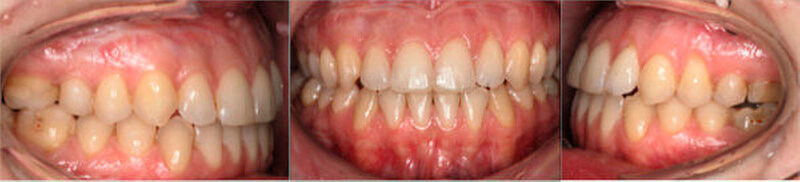

Anfangs wurde bei der Patientin eine transversale Expansion von etwa 5 mm mittels konventioneller GNE (Abbildung 3a) durchgeführt. Nach sechsmonatiger Retention durch Belassen der GNE-Apparatur konnte die individualisierte linguale Apparatur (Incognito, 3M Unitek, TOP-Service für Lingualtechnik GmbH, Bad Essen) eingesetzt werden (Abbildung 3b).

Entscheidend bei der präoperativen kieferorthopädischen Therapie war es, den Overbite offen zu halten und die negative sagittale Stufe durch Dekompensation der Incisivi-Position zu vergrößern, um die chirurgische Umstellung zu ermöglichen.